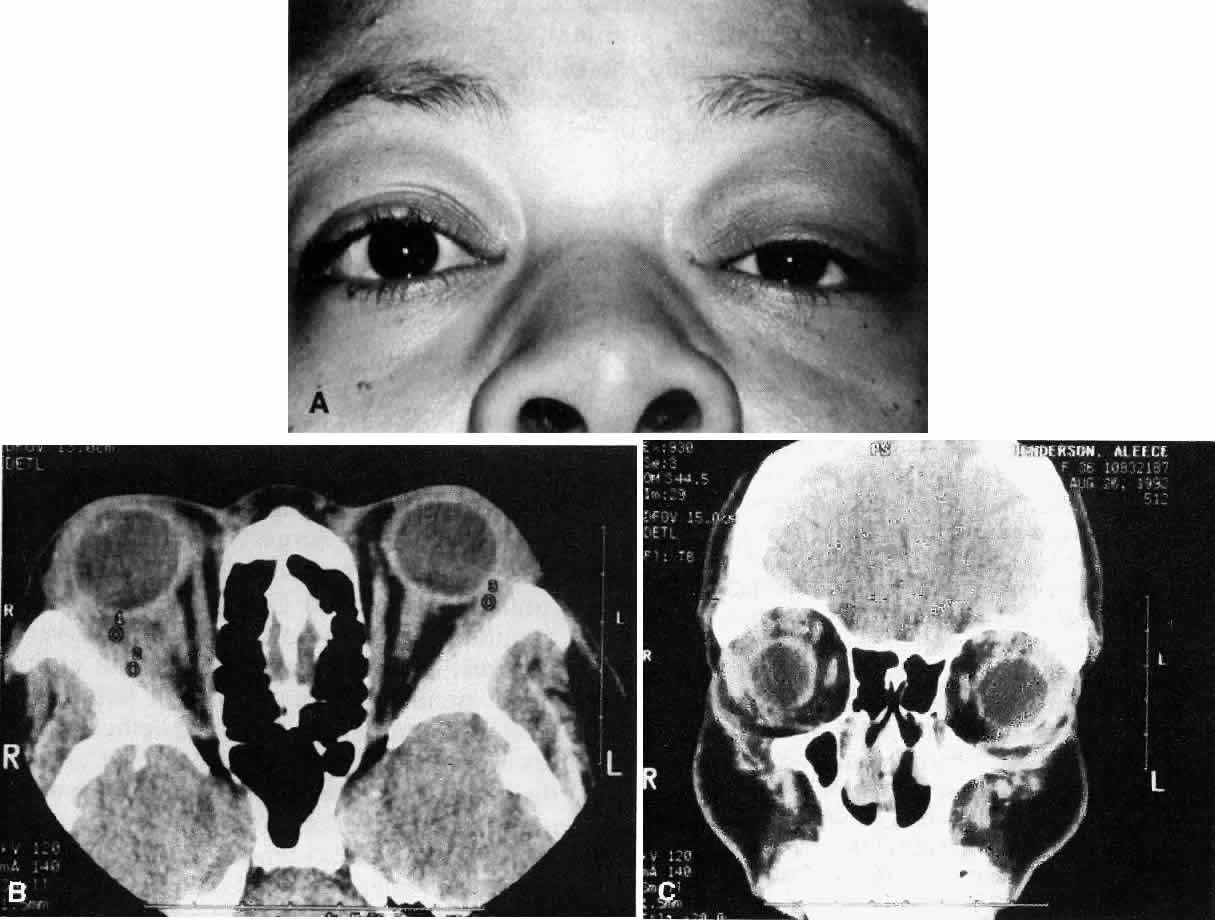

Wegener's granulomatosis is characterized by inflammatory lesions of the upper respiratory tract, lower respiratory tract, the kidneys, and, to varying degrees, generalized small vasculitis of other structures, including the eye (Figs. 10 AND 11). The definitive diagnosis is confirmed by biopsy. A limited form of the disease has been described that spares the kidneys.

Fig. 10. A. This 68-year-old woman presented with acute orbital inflammation, pain, and diplopia. Clinical evaluation demonstrated a medial orbital mass. Biopsy of the orbital mass demonstrated significant vasculitic and granulomatous changes believed to be consistent with Wegener's granulomatosis. No systemic disease was present. B. Appearance of same patient after treatment with prednisone and cyclophosphamide demonstrating complete resolution of the inflammatory process.

Fig. 11. A. This 31-year-old man has had Wegener's granulomatosis for 2 years. His disease process is stable on chronic corticosteroid therapy. He has no evidence of systemic disease. Note right-sided proptosis and hyperglobus. B. Profile of same patient demonstrating collapse of nasal bridge from bony destruction secondary to Wegener's granulomatosis. Note presence of swelling in lower eyelid. C. Axial CT image from the same patient demonstrating significant bilateral disease and bony destruction. Despite the extent of the orbital process on the right, the patient does not have diplopia. D. Coronal CT image showing destruction of medial orbital walls, vomer, and orbital septum. E. Pulmonary biopsy specimen from patient with orbital signs contains an almost obliterated vessel to right of center and scattered giant cells on left (H&E, ×160).

Ocular manifestations include orbital inflammation, scleritis, keratitis, and uveitis. The ocular involvement can occur from extension of sinus and nasal lesions or from focal small vessel vasculitis.